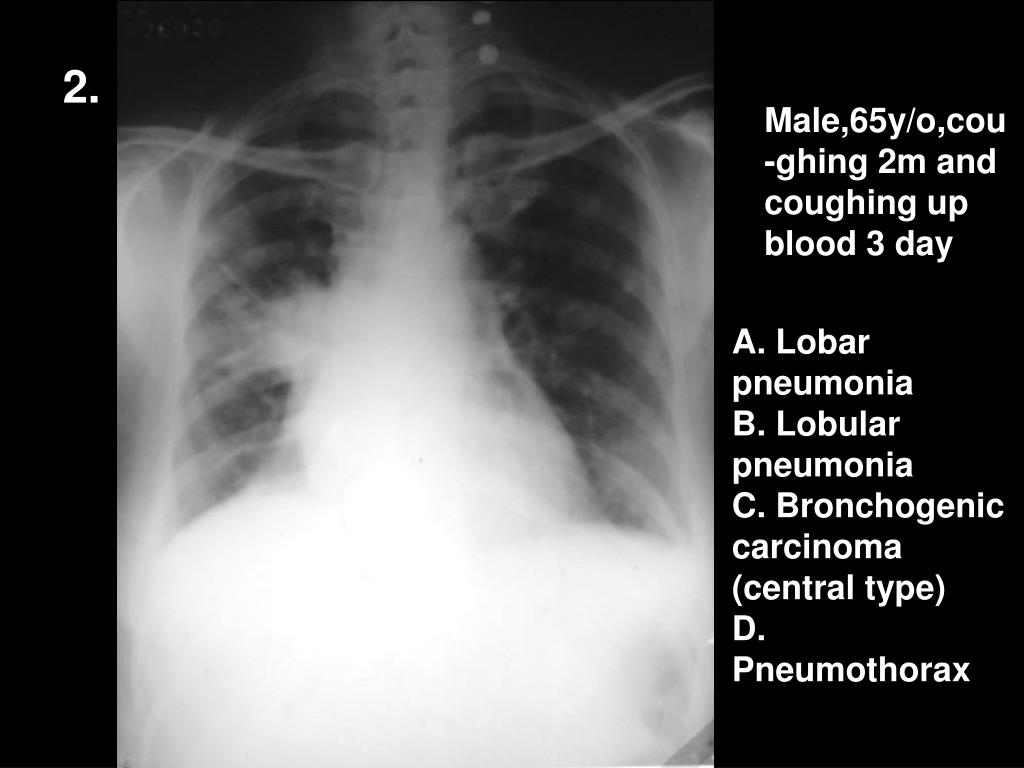

3. 2. Male,65y/o,cou-ghing 2m and coughing up blood 3 day A. Lobar pneumonia B. Lobular pneumonia C. Bronchogenic carcinoma (central type) D. Pneumothorax